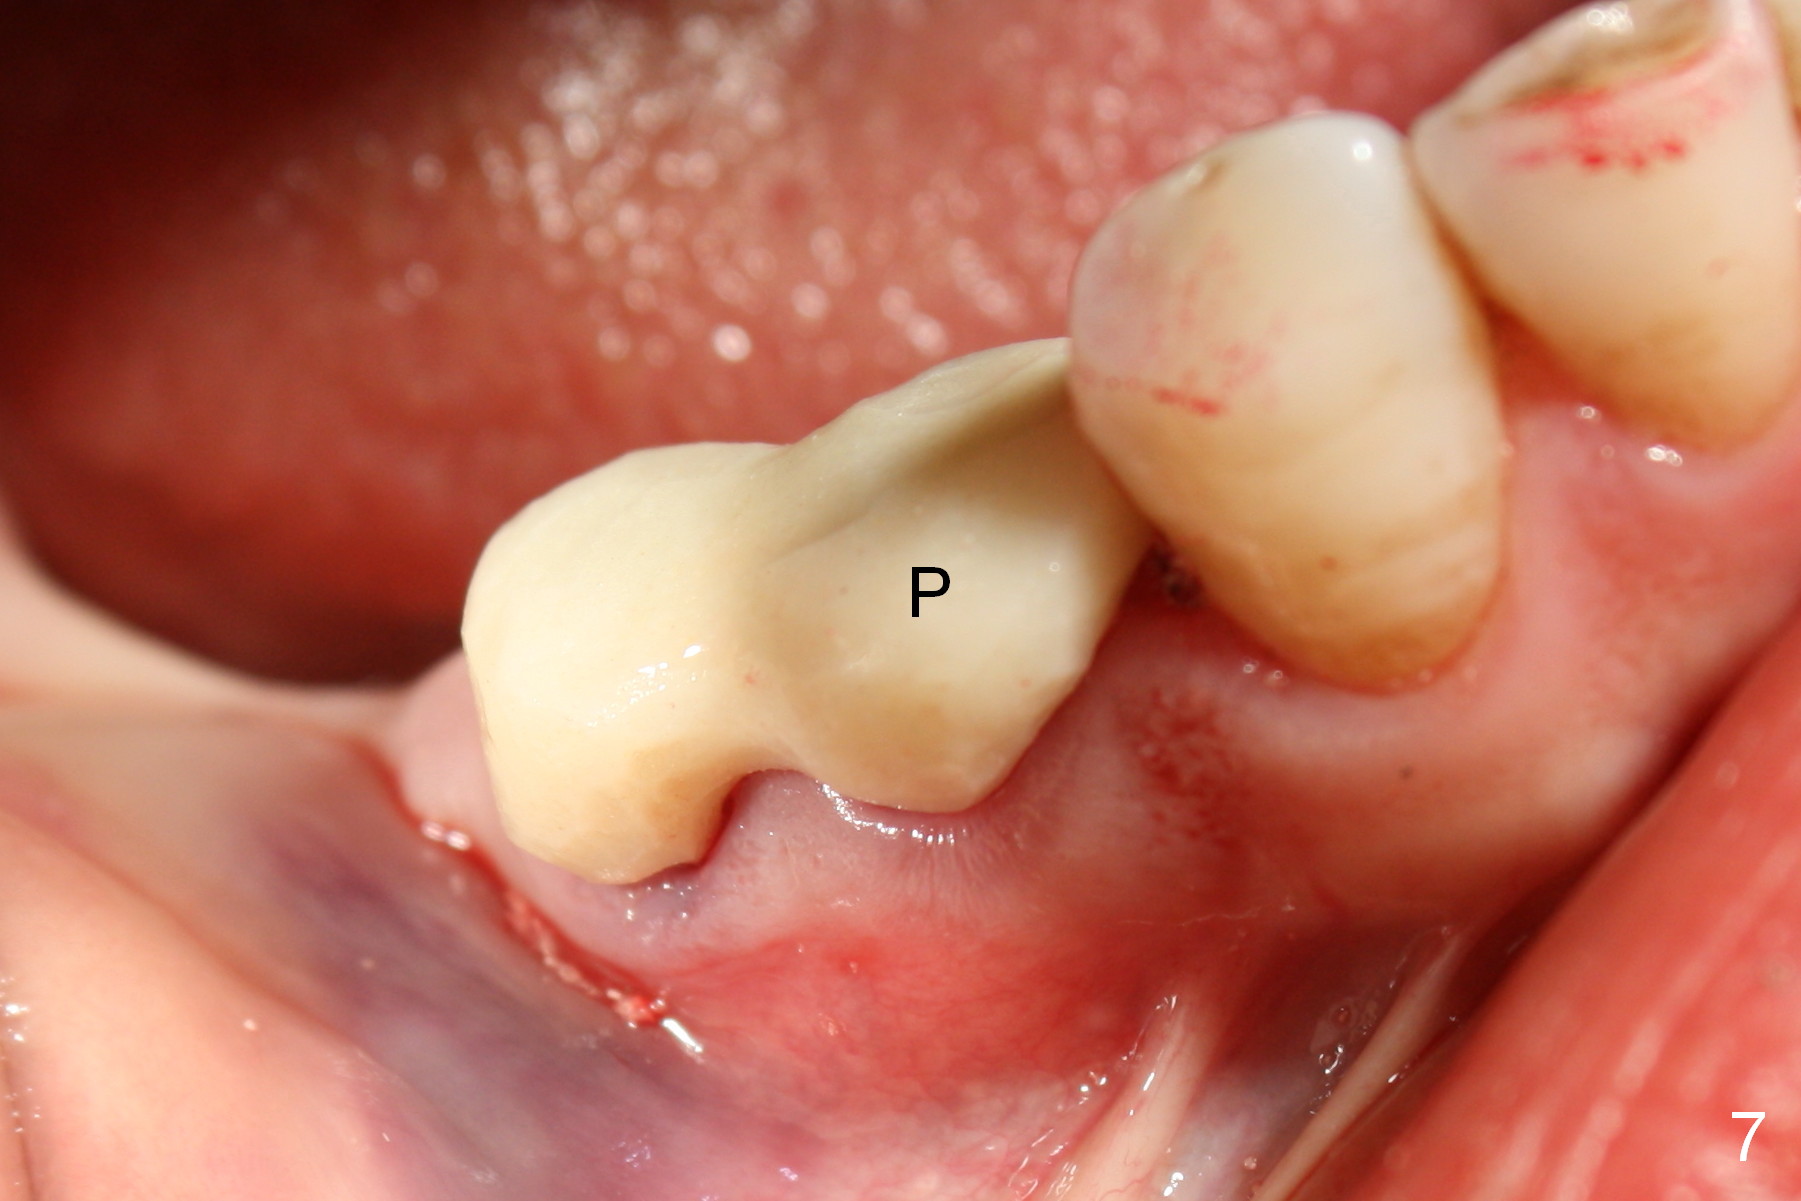

After restoring the implant at the site of #20, the patient returns for #28,29 implant placement (Fig.1,2). Bone level and distance from the Mental Loop (Fig.2 red dashed line) are different. It appears that longer implant can be placed at #28 than that at #29. Parallel pins are placed after initial osteotomy (Fig.3), it appears that the osteotomy at #29 should be moved mesially (arrow). Next PA shows that the position of the osteotomy at #29 is corrected (Fig.4). The position of the implants (4.5x17, 4.5x14 mm) appears ideal (Fig.5). After preparation for an immediate provisional, bone graft is placed in the remaining socket space (Fig.6 *). The splinted provisional is temporarily placed (Fig.7 P). The implant at #29 seems to be buccally placed. After CBCT confirmation, it should be removed for replacement. In addition to moving the osteotomy lingually, there is apparent space (~3 mm) to extend the osteotomy apcially for primary stability (Fig.8 arrow). The apical diameter of the implant is 3 mm.